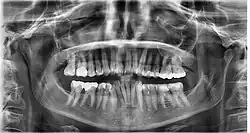

Dental